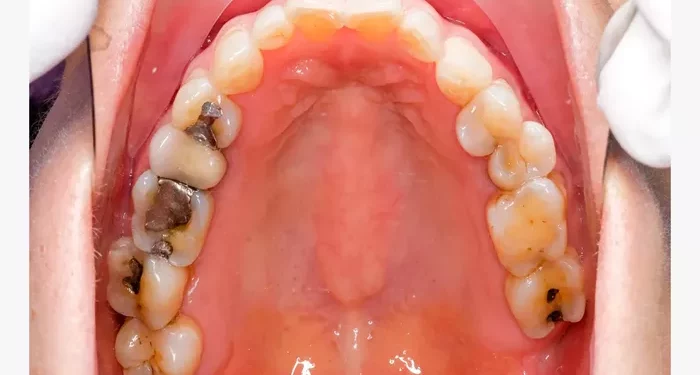

A cavity, also known as dental caries, is a damaged area in the hard surface of a tooth. Cavities are caused by the action of bacteria in the mouth. These bacteria produce acids that erode the tooth enamel, leading to decay. If not treated, cavities can lead to pain, infection, and tooth loss.

Cavities should not be ignored. They can worsen over time and lead to more serious issues, such as tooth abscesses or root canal infections. Addressing cavities early can save you from more extensive and costly procedures in the future. Regular dental check-ups are crucial for identifying cavities before they become severe.